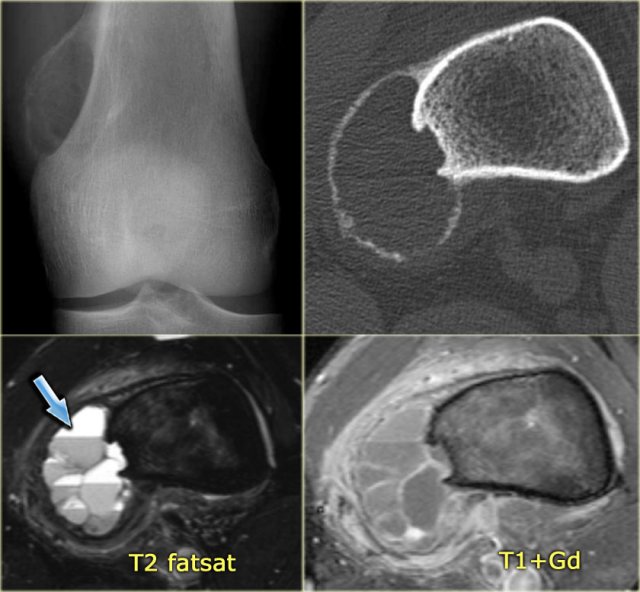

Chondroblastoma (7)

The images show a chondroblastoma in the patella.

Notice the extensive edema (blue arrow)